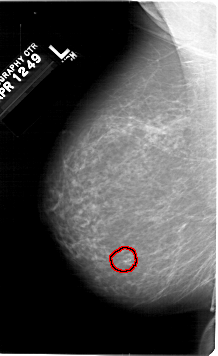

A_1307_1.RIGHT_CC

RIGHT_CC LINES 6016 PIXELS_PER_LINE 3376 BITS_PER_PIXEL 12 RESOLUTION 43.5 NON_OVERLAY

FILE: A_1307_1.LEFT_CC.OVERLAY

TOTAL_ABNORMALITIES 1

ABNORMALITY 1

LESION_TYPE CALCIFICATION TYPE PLEOMORPHIC DISTRIBUTION CLUSTERED

ASSESSMENT 4

SUBTLETY 4

PATHOLOGY BENIGN

TOTAL_OUTLINES 1

BOUNDARY